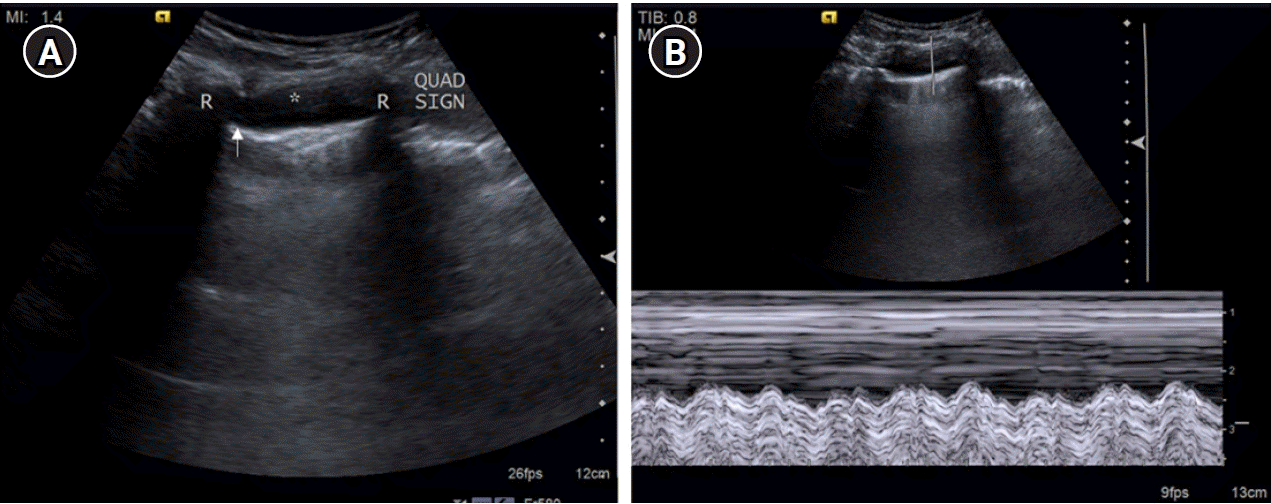

Figure 14.

posterolateral alveolar and/or pleural syndrome profile. (A) Pleural effusion (asterisk) in a 20-year-old female presenting with breathlessness and chest pain identified by visualizing the underlying visceral pleural line/“lung line” (arrow). “Quad sign,” a sonographic feature is depicted in the form of a rough quadrilateral bounded by the two ribs (R) with their posterior acoustic shadow on either side, the pleural line superiorly, and the lung line inferiorly. (B) M-mode tracing in a pleural effusion reveals a “sinusoidal” pattern. The underlying lung appears to be normal, with few Sub-B lines seen.

Four patterns of consolidation were described by Lichtenstein [1] to diagnose pneumonia. These included “non-translobar consolidation,” “translobar consolidation,” small subpleural consolidation identified by “C-line” and unilateral lung rocket pattern. To identify the “non-translobar” type of consolidation (Figure 15), presence of associated pleural effusion is first looked for by evidence of a regular lung line. This is done to avoid misdiagnosing a consolidation for an effusion. Traditionally, the diagnosis of pleural effusion is based on visualizing an anechoic/hypoechoic collection. This criterion is not advocated by the BLUE protocol, especially in critically ill patients with life-threatening collections like hemothorax and pyothorax and in challenging cases where difficulty in examination might create “parasite echoes” as described by Lichtenstein [7]. In the BLUE protocol, Lichtenstein [1] described the “lung line”, “quad sign” and “sinusoid sign,” as criteria for diagnosis of pleural effusion, disregarding the echogenicity of the collection (Figure 13).

The “Lung line” is a regular line which outlines the effusion, indicating the visceral pleural line, roughly parallel to the pleural line (parietal pleura). Thus, all effusions, anechoic or echoic, can be diagnosed using the lung line. Another useful sign is the “quad sign” which refers to the rough quadrilateral appearance of the effusion framed by the pleural line superiorly, visceral line inferiorly and rib shadows on either side. It is best demonstrated at the “PLAPS point” in a critically ill patient who has to be examined in a supine position.

A dynamic sign for diagnosing pleural effusion is the “sinusoid sign”. On M-mode, a “sinusoidal pattern” is noted due to movement of lung line towards the motionless pleural line on inspiration and downward movement on expiration, shaping a sinusoid. This sign is specific for pleural effusion. However, it is absent in very viscous or septate effusions. Moreover, since this sign indicates a low viscosity of fluid, the use of a narrow-gauge needle for thoracocentesis can be advised.